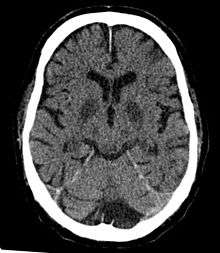

Cerebral hypoxia is a form of hypoxia (reduced supply of oxygen), specifically involving the brain; when the brain is completely deprived of oxygen, it is called cerebral anoxia. There are four categories of cerebral hypoxia; they are, in order of severity: diffuse cerebral hypoxia (DCH), focal cerebral ischemia, cerebral infarction, and global cerebral ischemia. Prolonged hypoxia induces neuronal cell death via apoptosis, resulting in a hypoxic brain injury.[1][2]

- Focal cerebral ischemia – A stroke occurring in a localized area that can either be acute or transient. This may be due to a variety of medical conditions such as an aneurysm that causes a hemorrhagic stroke, or an occlusion occurring in the affected blood vessels due to a thrombus (thrombotic stroke) or embolus (embolic stroke).[10] Focal cerebral ischemia constitutes a large majority of the clinical cases in stroke pathology with the infarct usually occurring in the middle cerebral artery (MCA).[11]

- Ischemic hypoxia ( or "stagnant hypoxia") – Reduced brain oxygen is caused by inadequate blood flow to the brain. Stroke, shock, cardiac arrest and heart attack may cause stagnant hypoxia. Ischemic hypoxia can also be created by pressure on the brain. Cerebral edema, brain hemorrhages and hydrocephalus exert pressure on brain tissue and impede their absorption of oxygen.